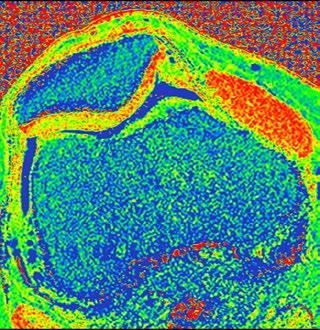

PD STIR - 1024 x 1024 matrix - 3mm slice thickness

Sag T2 - 0.5 x 0.5 min - 0:56 min Ax PD FatSat - 0.6 x 0.6 mm - 1:30 min Cor PD FatSat - 0.6 x 0.6 mm - 1:15 min Cor PD - 0.5 x 0.5 mm - 0:58 min © 2020 CANON MEDICAL SYSTEMS // MREU200040

Fast knee protocol with AiCE on Vantage Orian 1.5T

Standard Image 1 Average - 1:45 min Improved quality by AiCE 1 Average - 1:45 min Improved quality by long scan times 10 Averages - 16:49 min

Prof. Garry E. Gold, Clinical radiologist and researcher, Past president of the International Society for Magnetic Resonance in Medicine (ISMRM) and the Society of Computed Body Tomography and Magnetic Resonance (SCBT/MR)